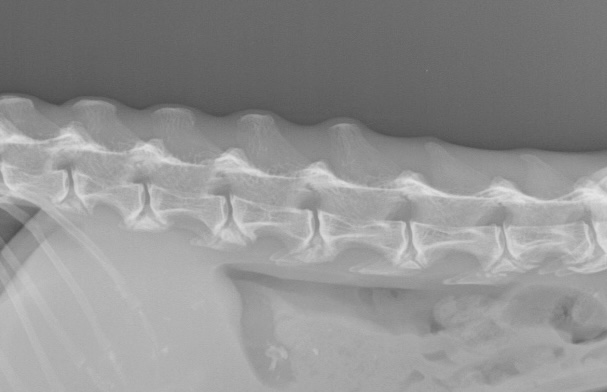

猫は後肢だけではなく前肢の肘や肩、手首(手根)にも関節炎が起き、慢性的な痛みによって日常生活に大きな支障がでることもあります。

またレントゲン検査では、骨や関節の変形が起きてからでないと異常が分からないことが多いため、こちらも関節炎の早期発見には不向きです。

視診、歩行検査、触診、整形外科的検査、レントゲン検査などを組み合わせて総合的に判断する必要があります。